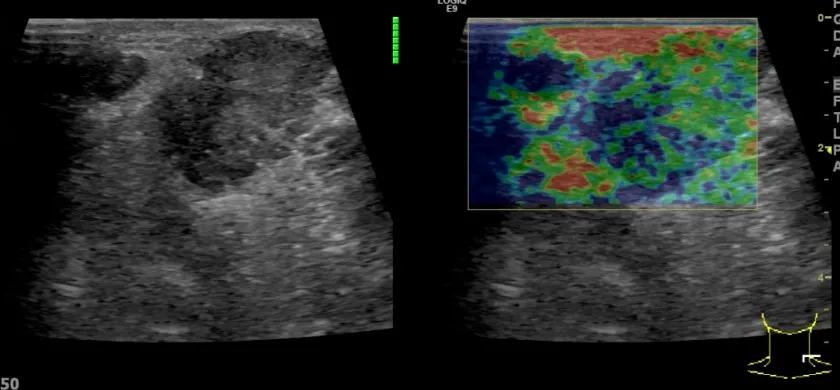

随后,徐栋教授进一步分享了五个临床实战病例,带来了更直观的热消融治疗经验。第一个病例是62岁肺癌患者,术后1年余发现双侧锁骨上淋巴结复发,侵犯神经,存在静脉回流、淋巴回流障碍,肿胀、疼痛非常明显。影像显示患者淋巴结边界不清、形态不规则,存在浸润,血流强化增强。由于患者在系统治疗后进展,且主要目的缓解症状、减瘤。局麻下行热消融术,从后向前逐层消融,热消融之后超声造影即刻评估显示完全充盈缺损,完全覆盖病灶。

(病例1图例)